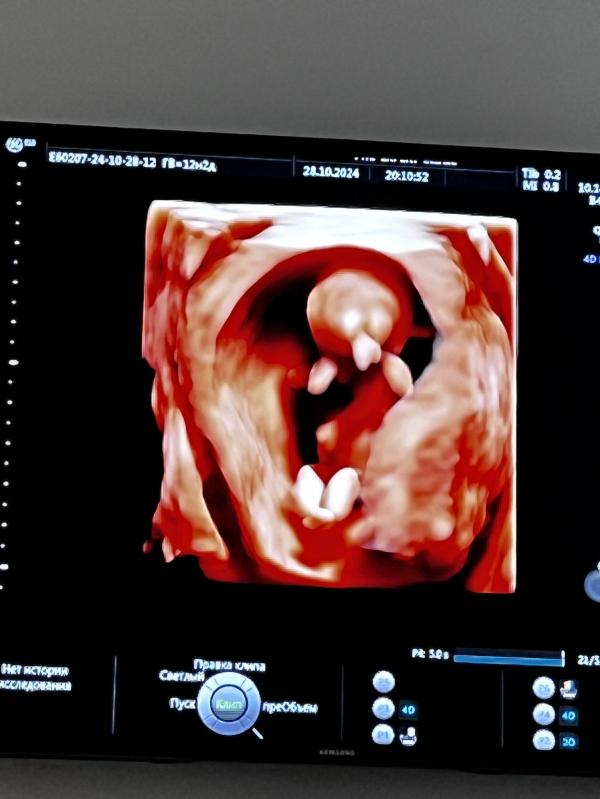

УЗИ показало, что у малыша все хорошо! Носик, все в порядке, душа спокойна после обследования!

Девочки добрый вечер!) была на узи сегодня, узнала что все хорошо все как надо у малыша 😍 душа спокойна! А то видео попадутся ужасные и переживала) носик и тд все показали🥹